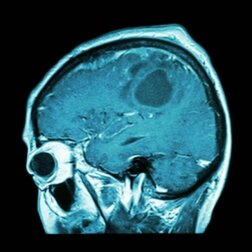

Il glioblastoma è uno dei tumori più aggressivi. Per ottenere esiti favorevoli, i volontari che hanno preso parte allo studio avevano bisogno di un vaccino personalizzato. In che modo, però?

Il modo migliore consiste nel formulare un vaccino utilizzando gli antigeni del tumore del paziente. Questa operazione fornisce una risposta immunitaria molto più efficace. I linfociti, infatti, riescono a riconoscere le cellule “cattive” e le distruggono.

Nel corso della ricerca ci si è accorti che i pazienti rispondevano in modo favorevole al vaccino personalizzato e non a quello generico. In altre parole, un vaccino formulato per qualsiasi neoplasia non è efficace. Per distruggere il tumore al cervello, il vaccino deve essere personalizzato.

Oltre a ciò, è importante ricordare che durante lo studio non è stato possibile curare il cancro dei volontari. Bisogna sottolineare, tuttavia, che il glioblastoma è un tumore molto aggressivo, con un alto tasso di mortalità nonostante i trattamenti portati a termine.

Si è però riusciti ad aumentare il tasso di sopravvivenza. In genere un individuo affetto da glioblastoma ha un’aspettativa di vita pari a 14 mesi. Il vaccino ha permesso di raggiungere i 29 mesi. Si tratta indubbiamente di un dato incoraggiante, che indica che ci troviamo sulla strada giusta e che la cura definitiva potrebbe essere vicina.